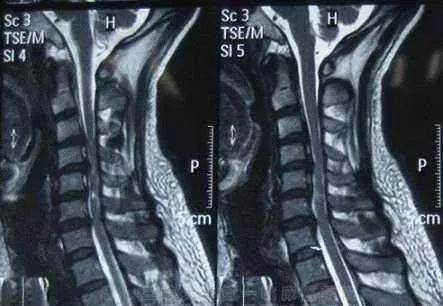

4.脊髓型颈椎病

髓型颈椎病的发病率占颈椎病的12-20%,也是目前许多骨科,和大夫非常头痛的一种颈椎病类型,因为他的影响十分严重。甚至可造成肢体瘫痪,脊髓型颈椎病致残率高。

脊髓型颈椎病通常起病缓慢,以40-60岁的中年人为多。脊髓型颈椎病的发病,和严重程度,往往和有无颈椎管狭窄有很大关系。

临床表现 :

1)多数患者首先出现一侧或双侧下肢麻木、沉重感,随后逐渐出现行走困难。上下楼梯时需要借力。严重者步态不稳、行走困难。患者双脚有踩棉感。

2)出现一侧或双侧上肢麻木、疼痛,双手无力、不灵活,像写字、系扣等精细动作难以完成。严重者甚至不能自己进食。

3)躯干部出现感觉异常,患者常感觉在胸腹部、或双下肢有如皮带样的捆绑感。同时下肢可有烧灼感、冰凉感。

4)部分患者出现排尿无力、尿频尿急、尿不尽、尿失禁或尿潴留等排尿障碍,大便密结等,性功能减退。